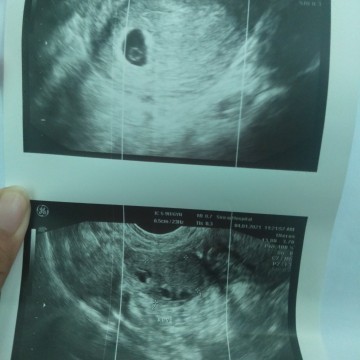

อันนี้เราไปหาหมอ เราตั้งท้องได้ประมาน6สัปดาห์ หมอซาวด์จะช่องคลอด หมอบอกว่ายังไม่เห็นตัวเด็ก เห็นแต่ถุงการตั้งครรภ์..แล้วหมอก้อพูดลงท้ายว่า..เด่วมันอาจจะฝ่อและหลุดออกไปเอง ซึ่งหมอไม่ได้อธิบายอะไรต่อ ทำให้เราเครียดแระสงสัยว่าทำไมหมอถึงพูดแบบนั้น.. ท้องนี้เป็นท้องแรกของเรา แม่ๆท่านอื่นช่วยแนะนำหน่อยน่ะค่ะ